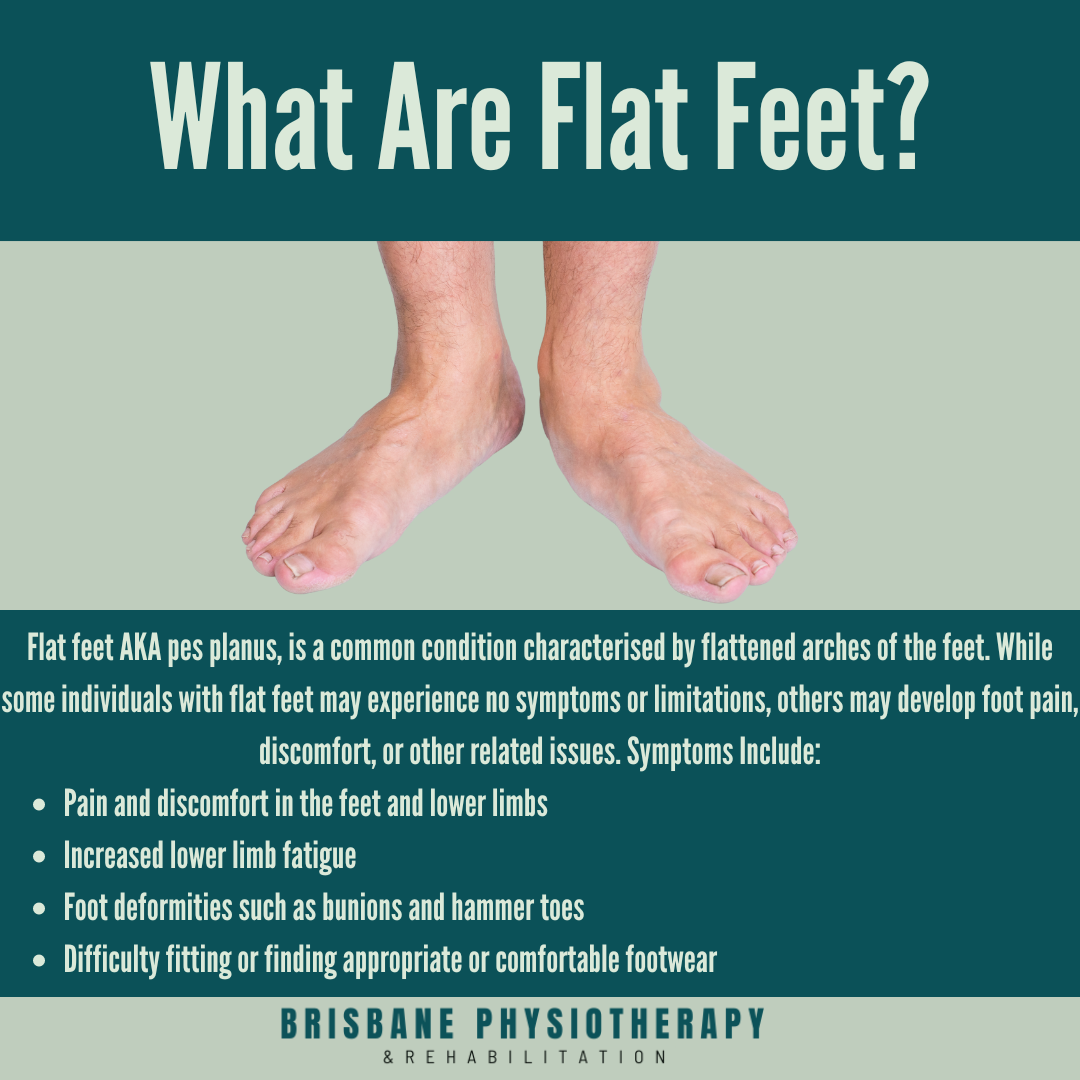

Flat Feet Causes Symptoms Treatment Brisbane Physiotherapy

Product Name: Flat foot pain treatment new arrivalsFlat Feet Causes Symptoms Treatment Brisbane Physiotherapy new arrivals, 10 Tips To Help You If You Have A Flat Foot Beltsville Foot and Ankle Center Podiatrists new arrivals, Treating the Flat Foot Chelsea and Westminster Hospital NHS Foundation Trust new arrivals, Flat Feet Diagnosis and treatment Dr Kong Official new arrivals, 7 Best Flat Feet Treatments Ask Doctor Jo new arrivals, Treatments for Flat Feet The Podiatry Group of South Texas new arrivals, Flatfeet Specialist in Gilbert Scottsdale Chandler Mesa Phoenix new arrivals, How to Ease Pain Caused by Flat Feet and Arthritis Foot Levelers new arrivals, Flat Feet Flatfoot Types Causes Treatment new arrivals, Relieve the Pain of Flat Feet with Physical Therapy new arrivals, How We Treat Flat Feet Collapsed Arches Physical Therapy new arrivals, Flat feet Symptoms exercises diagnosis and treatment new arrivals, Flat Feet Flat Feet Treatment Painful Feet Tired Feet new arrivals, COIF Leg Splint Flat Feet Pain Relief Feet Band High Flat Arch Support Band Foot Support Buy COIF Leg Splint Flat Feet Pain Relief Feet Band High Flat Arch new arrivals, Transform Your Foot Health with Orthopaedic Insoles Podogo new arrivals, Flat Feet Treatment in Uttam Nagar or Physiotherapist in Uttam Nagar Archives Dr NasirPhysiotherapy and Rehabilation new arrivals, Flat feet NHS new arrivals, Flat Feet Treatment Edmonton Alberta The Foot Institute new arrivals, Amazon Orthotic Flat Feet Arch Support Insoles Metatarsal Orthotic Insoles Arch Supports Inserts for Metatarsalgia Plantar Fasciitis Ball of Foot Pain Relief Morton s Neuroma Shoe Inserts Health H... new arrivals, Dr. Frederick s Original Arch Support Sleeves Plus 2 pcs Arch Pain Relief Flat Foot Support Arch Supports for Men Women Small Medium Walmart new arrivals, Flat feet NHS new arrivals, 2x ORTHOTIC FOOT SUPPORT INSOLE FOR MEN WOMAN FLAT FEET HEEL ARCHES PAIN RELIEF eBay new arrivals, Five Steps for Alleviating Flat Feet Pain University of Utah Health new arrivals, Flat Feet Need an Arch Maple Springs Foot Center new arrivals, Flat Fleet Treatments new arrivals, Visit Body Works Physiotherapy to Try Custom Orthotics for Flat Feet new arrivals, Flat Feet Explained Diagnosis Treatment and Prevention Maple Healthcare Vietnam new arrivals, Orthotic Insoles for Flat Feet Plantar Fasciitis Pain Relief for Men and Women new arrivals, Brace Support Cushioned Foot Pad Flat Feet Foot Care Pain Relief Wrap Pads Targeted Pressure Point Relief Fallen Arch Support Cushions new arrivals, Flat Foot and High Arches Treatment Penn Medicine new arrivals, Plantar Fasciitis Treatment Symptoms Causes Prevention PediFix new arrivals, Mid Foot Pain Causes Symptoms Best Home Treatment new arrivals, Treating the Flat Foot Chelsea and Westminster Hospital NHS Foundation Trust new arrivals, Buy Flat Foot Arch Support for Men Women Medical Arch Support for Flat Feet Correction Sleeve with Cushion Leg Foot Pain Relief Product Foot Care for Orthopaedic Shoes Slippers Foot Arch new arrivals, Flat Feet Pain Treatment Hyperhealth new arrivals.